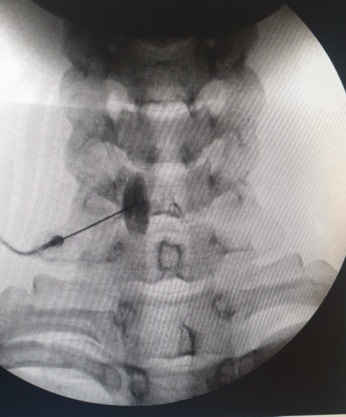

Τα οσφυϊκά συμπαθητικά γάγγλια εδράζονται στο προσθιοπλάγιο τριτημόριο του δεύτερου, τρίτου και τέταρτου οσφυϊκού σπονδύλου. Με τον ασθενή σε πρηνή θέση και με τοπική αναισθησία, εισάγονται κάτω από ακτινοσκοπικό έλεγχο διαδοχικά 3 βελόνες, οι οποίες προωθούνται στα πλάγια τον σπονδυλικών σωμάτων με το άκρο τους να φθάνει στο πρόσθιο 1/3 των σπονδυλικών σωμάτων. Χορηγείται σκιαγραφική ουσία και επί ικανοποιητικής απεικόνισης, χορηγείται το διάλυμα τοπικού αναισθητικού και στεροειδούς. Για μακρά θεραπευτική δράση, απαιτούνται διαδοχικές συνεδρίες φαρμακευτικού αποκλεισμού ή νευρόλυση με χρήση ραδιοσυχνοτήτων.